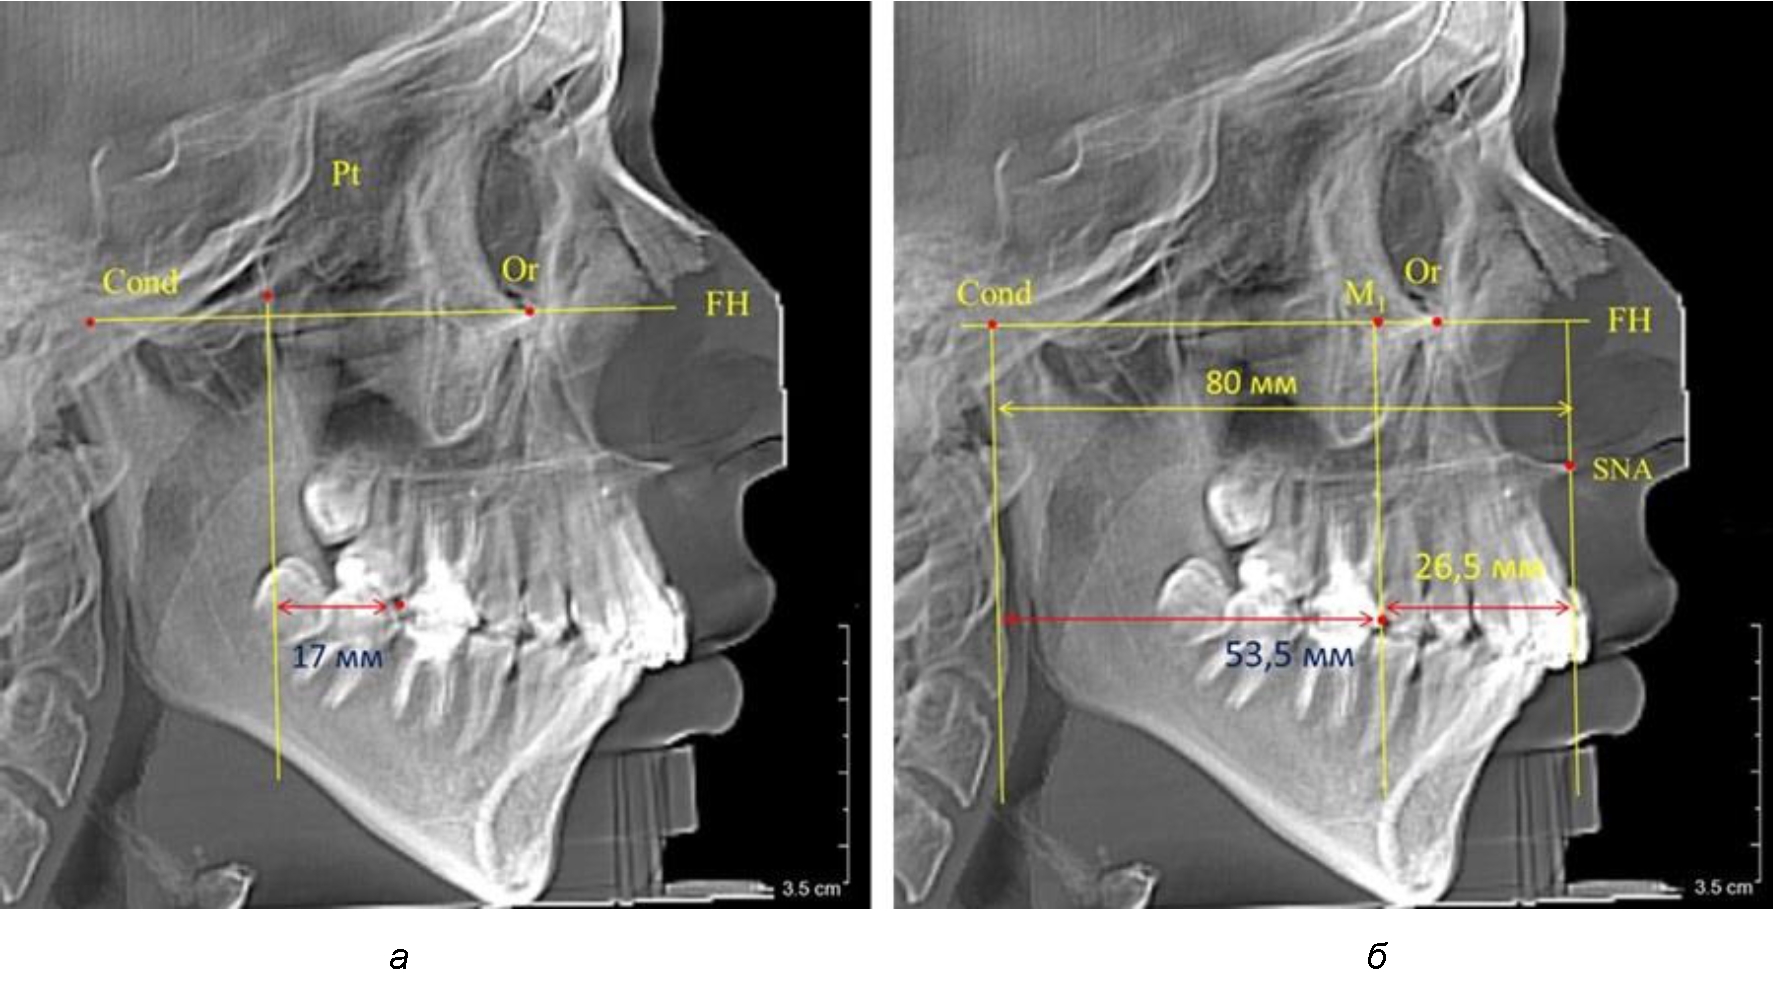

В то же время при увеличенном расстоянии от крыловидной вертикальной плоскости PTV до дистальной поверхности верхнего первого постоянного моляра, равное 23 мм, сагиттальный размер гнатического отдела составил 92 мм. При этом отношение кондилярно-спинального расстояния к кондилярно-молярному размеру (30,5), так же, как и при малых размерах, было близким к коэффициенту 1,5, что представлено на рис. 3.

Рис. 3. Особенности положения первых моляров по R. E. McDonald (а) и по предложенному методу (б) при увеличенном молярно-крыловидном расстоянии

По мере роста челюстей увеличивалась глубина гнатического отдела лица, и кондиллярно-спинальный размер составлял в среднем (74,57 ± 0,93) мм. Дистальная поверхность первого постоянного моляра отстояла от крыловидной вертикали на величину, составляющую около 11 мм, что, так же, как и в периоде прикуса молочных зубов, было близким по значению к данным R. E. McDonald, а именно возраст, плюс 3 мм. Однако величина ошибки среднего значения свидетельствовала о вариабельности признака даже в восьмилетнем возрасте после замены передней группы зубов и установки ключевых постоянных моляров в окклюзионное равновесие. Обращает на себя внимание отношение глубины гнатического отдела лица к дистальному отделу, а именно к кондилярно-молярному расстоянию (рис. 5).